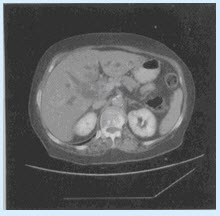

患儿,女,15岁。反复发作黄疸、胆道感染,行CT检查如图所示。

(单选题)该患者结合临床和影像应考虑()

C:脾囊肿